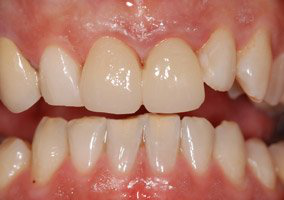

Cas 3 : Couronne toute céramique sur inlay-core céramisé et facette céramique sur deux incisives centrales chez un homme

La réalisation concomitante avec la même céramique usinée sur deux incisives centrales supérieures d’une couronne céramique sur dent dépulpée et d’une facette sur dent vivante permet d’optimiser le rendu esthétique du sourire